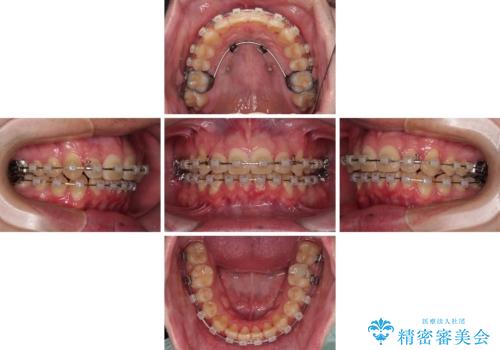

上顎前歯のデコボコを改善してスッキリした口元に ワイヤー装置での非抜歯矯正

上下前歯にデコボコがありましたが、特に上顎の叢生が強く、通常に歯列を整えると、上顎が前方に突出し、口元の突出感が残った仕上がりとなる可能性が考えられました。

補助装置を用いて上顎歯列全体を後方に移動させる力をかけ、唇が閉じやすいような仕上がりを目指して、ワイヤー装置にて矯正治療を行うこととしました。

非常に咬合力が強く、左側の臼歯がなかなか後方へ移動できなかったのですが、2年ほどかけて大変満足のいく仕上がりを達成することができました。